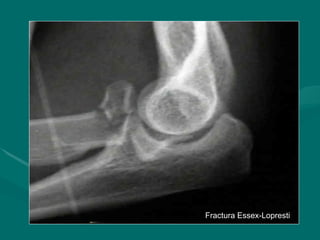

Fractura Essex-Lopresti

• Fractura conminuida de la cabeza

Fractura conminuida de la cabeza

radial asociada con subluxacion de la

articulacion radioulnar distal

• Usualmente asociado con la desviacion

Usualmente asociado con la desviacion

radial de la mano

• En las fracturas conminutas

En las fracturas conminutas

de la cabeza de radio debe ser

indispensable una examen radiológico

de la muñeca

Fractura Essex-Lopresti Fractura Essex-Lopresti •Fractura conminuida de la cabeza Fractura conminuida de la cabeza radial asociada con subluxacion de la radial asociada con subluxacion de la articulacion radioulnar distal articulacion radioulnar distal • Usualmente asociado con la desviacion Usualmente asociado con la desviacion radial de la mano radial de la mano • En las fracturas conminutas En las fracturas conminutas de la cabeza de radio debe ser de la cabeza de radio debe ser indispensable una examen radiológico indispensable una examen radiológico de la muñeca de la muñeca